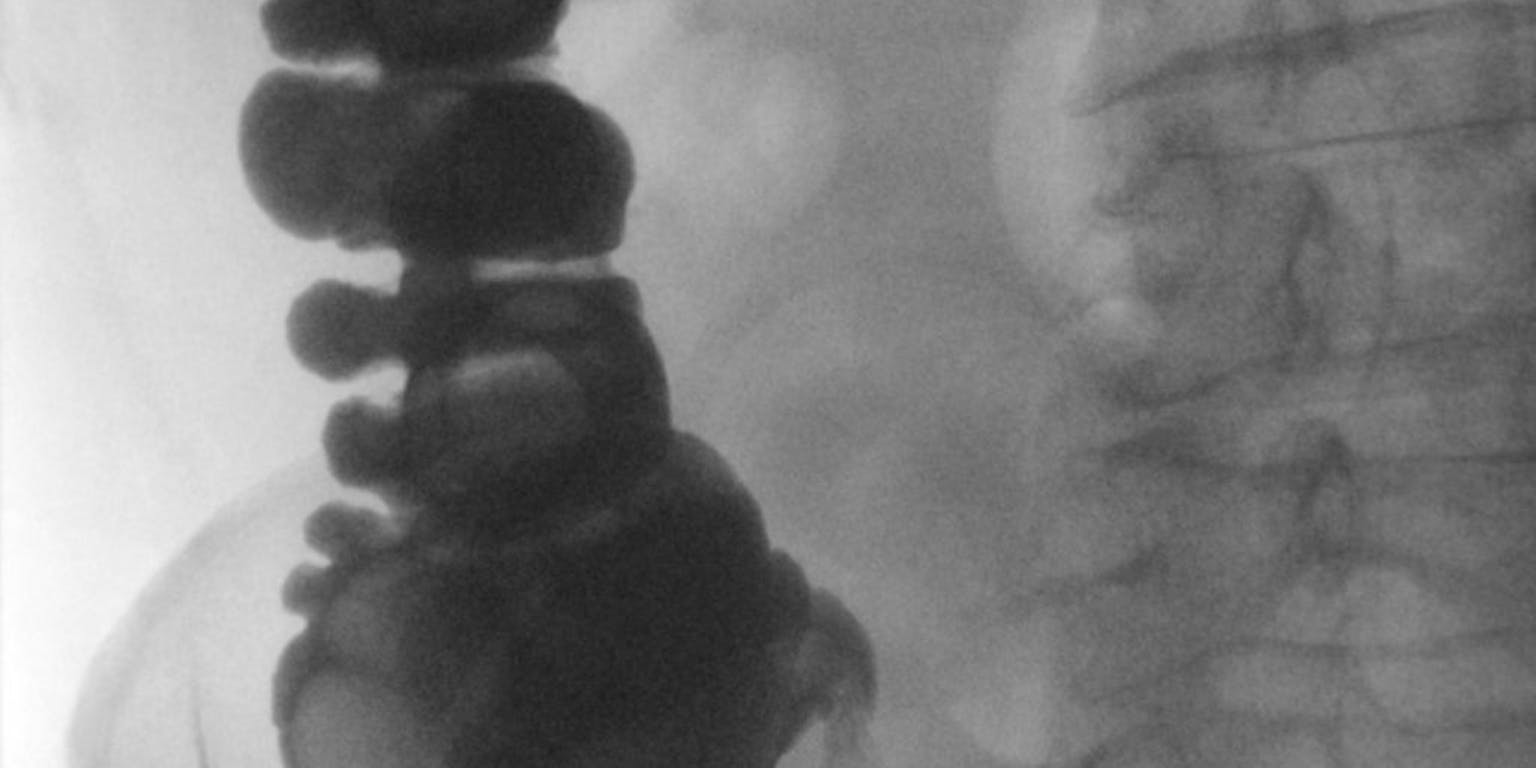

“We halen cellen uit het rechteratrium van het hart”, vertelt Goumans. “Daar ligt een gebiedje dat we ‘de blinde darm van het hart’ noemen. We weten niet goed wat de functie is, maar tijdens openhartoperaties wordt dat stukje altijd verwijderd. Nu gooien de chirurgen dit ‘afval’ niet weg, maar brengen het naar ons lab.”

In het verwijderde stukje hartweefsel zitten stamcellen, al zijn het er weinig. “We isoleren de aanwezige stamcellen, kweken ze zodat we er heel veel van krijgen en proberen ze dan met groeifactoren om te vormen tot hartspiercel of bloedvatcel”, zegt Goumans.